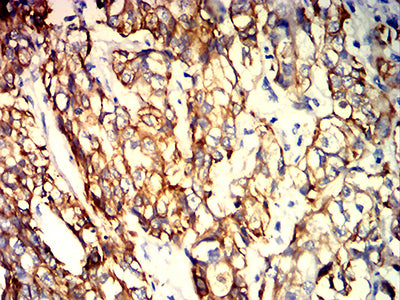

分类: 科研抗体货号: 32023别名: BIE; EHK; K10; KPP; BCIE; CK10应用: WB,IHC,IF,FCM反应种属: Human